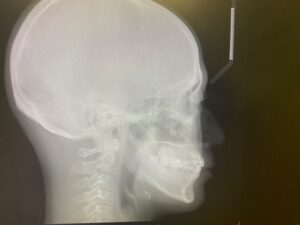

② レントゲン(正面セファロ・側面セファロ・パノラマ)

⑤ その他、必要に応じCTスキャンを利用した気道分析